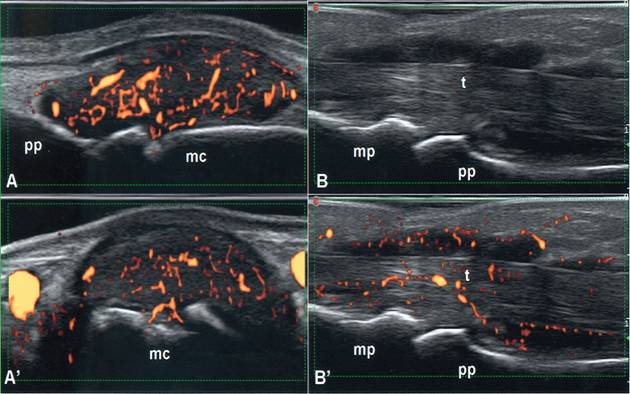

Trả lời: Trước hết chúng tôi rất cảm ơn câu hỏi của bạn, liên quan đến vấn đề siêu âm da để đánh giá gián tiếp hình ảnh và loại thương tổn da và các cơ quan liên quan trong các bệnh lý da hiện nay. Trên thực tế có thể sử dụng nhiều cách siêu âm da, nhân đây chúng tôi xin giới thiệu với bạn về siêu âm da bằng máy UV Scanner. Trên thực tế, rất ít người hiểu chính xác về tình trạng làn da của mình, da không chỉ bảo vệ cơ thể mà còn là tiếng nói cho sức khỏe và là yếu tố tiên quyết tạo nên vẻ đẹp thẩm mỹ. Chúng ta luôn âu lo khi thấy da xuất hiện những dấu hiệu xấu nhưng lại không biết nguyên nhân xuất phát từ đâu. Siêu âm da là cách để bạn giải tỏa những băn khoăn này và xác định được phương pháp chăm sóc điều trị da thích hợp, tiết kiệm thời gian, chi phí, đem lại hiệu quả cao.

Công nghệ siêu âm UV Scaner sử dụng thiết bị đa cảm biến, cùng lúc chẩn đoán về độ ẩm, độ đàn hồi, độ sáng, nhiệt độ của da, kích cỡ lỗ chân lông. Với hiệu ứng 3D, hiển thị hiệu ứng tần số về tình trạng da, cùng chức năng tia tử ngoại giúp đo từng nanomet của lỗ chân lông, nếp nhăn và sự biến đổi sắc tố. Đặc biệt, máy có thể chẩn đoán chính xác da ngay cả khi bạn đã trang điểm. Trong khi các máy thông thường chỉ có thể đo lường trên bề mặt như kiểm soát mụn, vết thâm và khó dự đoán được mức biến đổi da của bạn trong tương lai thì chiếc máy này không chỉ dự đoán được mức lão hóa của da bạn mà còn kiểm soát sâu, toàn bộ tình hình và các bệnh lý về da, từ đó các bác sĩ sẽ cho bạn lời khuyên về chế độ chăm sóc kịp thời và hợp lý nhất.

Trên đây là một ví dụ cho thấy siêu âm có thể đơn thuần hoặc phối hợp trong chẩn đoán và điều trị một số bệnh ngoài da có giá trị. Bạn có thể tìm đọc thêm trên các trang mạng với từ khóa google.com/ skin ultrasound